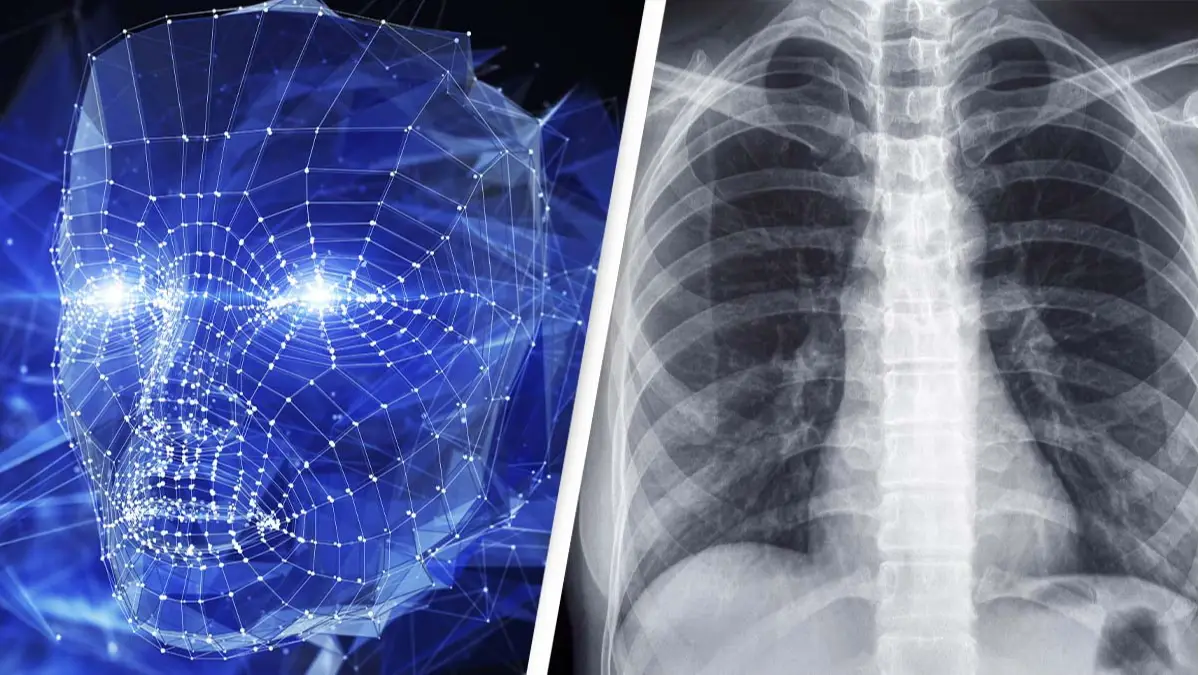

A new study has found that artificial intelligence (AI) diagnostic systems could produce racially-biased medical results that could result in adverse health issues.

Scientists and researchers at Harvard University have found that AI programs can determine a person’s race with more than 90% accuracy from an X-ray, a concept that is concerning scientists.

The research team trained the AI programs using standard X-rays and CT scans of different parts of the body. Each image was labelled with the race self-reported by the patient, but contained no traces of racial markers such as skin colour, bone density or hair texture.

The team found that the AI systems were astonishingly able to determine the race of the patient with an accuracy of more than 90%.